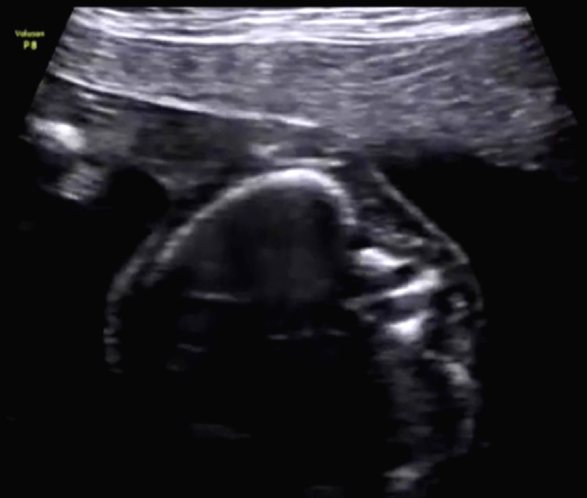

Figure 4. First view of axial section of the fetal spine. (Image courtesy of Firoz Bhuvar, MD)

Meningocele is characterized by spina bifida and herniation of the meninges through a spinal defect, but that does not seem to be the case here. To be sure, let's look at Figure 4, Figure 5, and Figure 6, which are axial images of the fetal spine.

After studying the aforementioned images, there is no obvious herniation of the meninges through a dorsal or ventral defect in the spine. However, there is an obvious anomaly visible in the images of the axial section of thoracic vertebrae, which was also visible in the images of the coronal section of the thoracic vertebrae. The anomaly is some form of division of the spinal canal.

Could this be hydromyelia, which is characterized by dilation of the central canal of the spinal cord? Or is it diplomyelia, which is division of the cord into two complete halves? Diplomyelia is possible, since there is a division of the cord in the region of the affected thoracic spine.

True diplomyelia is characterized by near-total division of the spinal cord, which is not the case here. The division is localized to the affected lower thoracic spines. In addition, there is a vertical echogenic, possibly bony, septum within the affected thoracic vertebrae. This finding suggests the possibility of diastematomyelia. This condition is seen as a partial or complete bony septum or fibrous septum that divides the spinal canal (localized to affected spine), with partial division of the spinal cord in the affected parts only.

To review, the findings in this fetus include the following:

- Midline bony spur or septum in the lower thoracic spine.

- Normal central canal of the spinal cord.

- No significant dilatation of cerebral ventricles.

- Division of the spinal cord localized to the affected thoracic spines.

- Normal spinal cord above and below the affected vertebrae.

The most common anomaly associated with these findings becomes our final diagnosis, which is diastematomyelia.